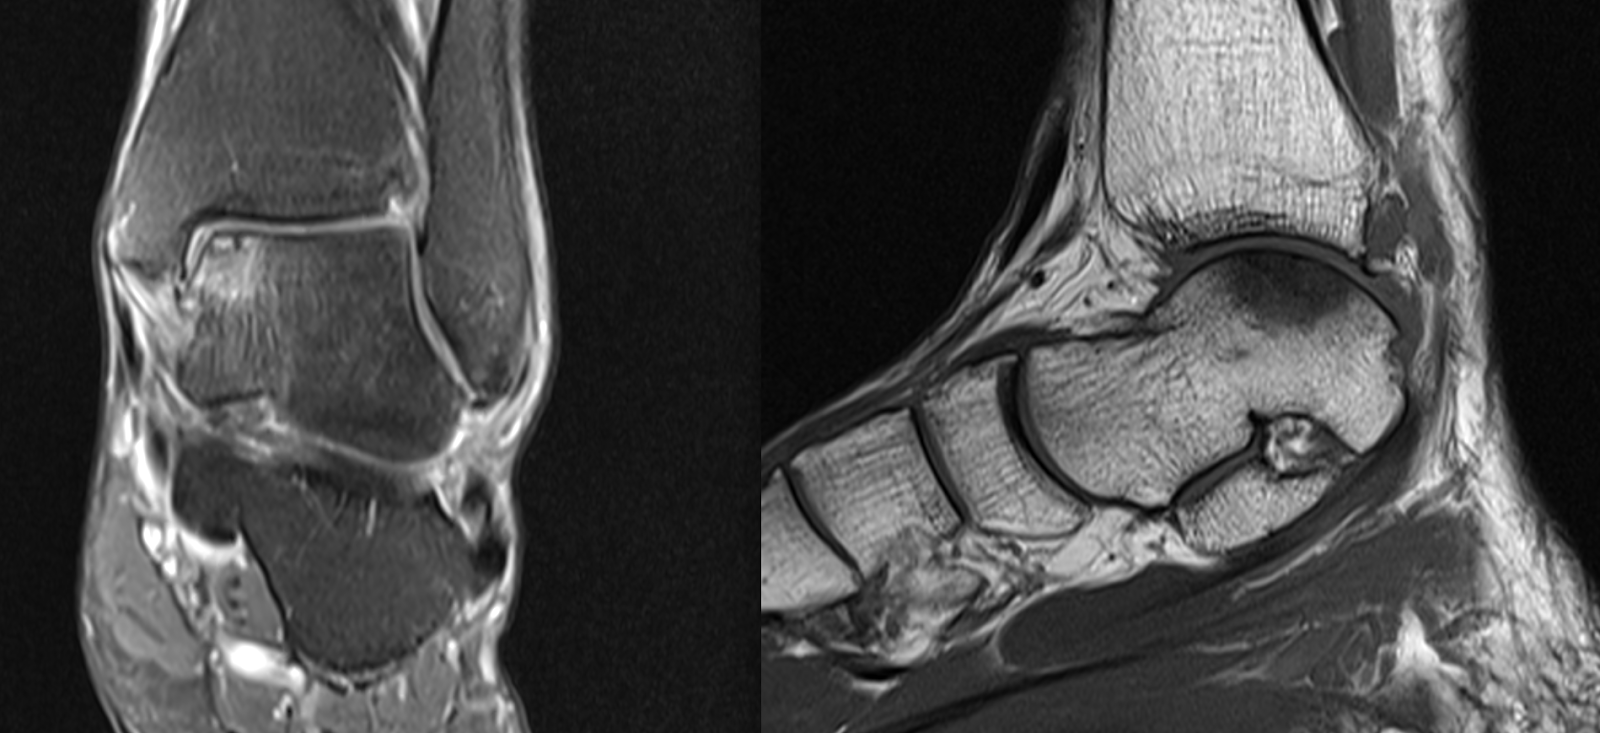

Ankle Osteochondral Defects / OCD

I have attached imaging of some recent osteochondral lesions that have been treated at our hospital.